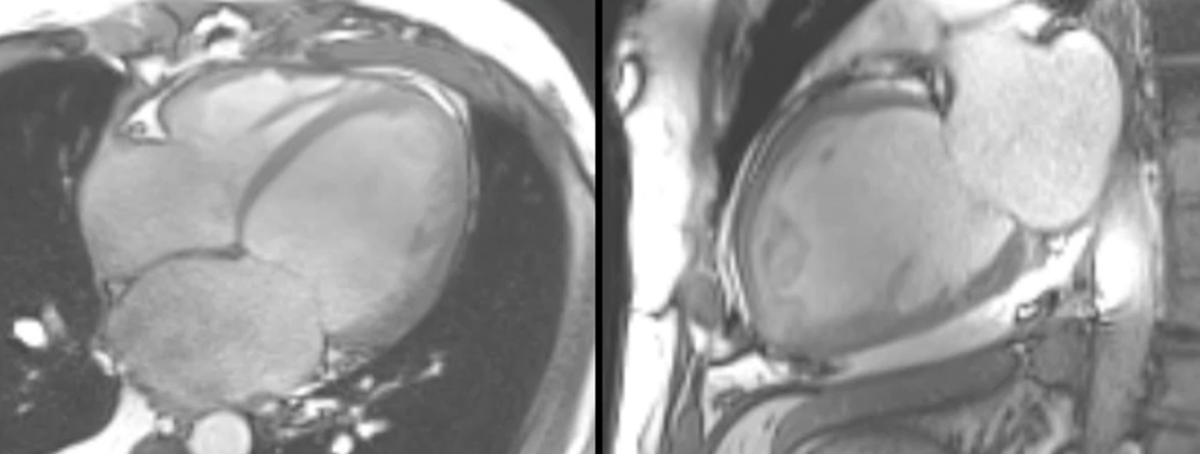

COD 077 - Decoding Septum Predominant Hypertrophic Cardiomyopathy

Understanding standard septum predominant HCM